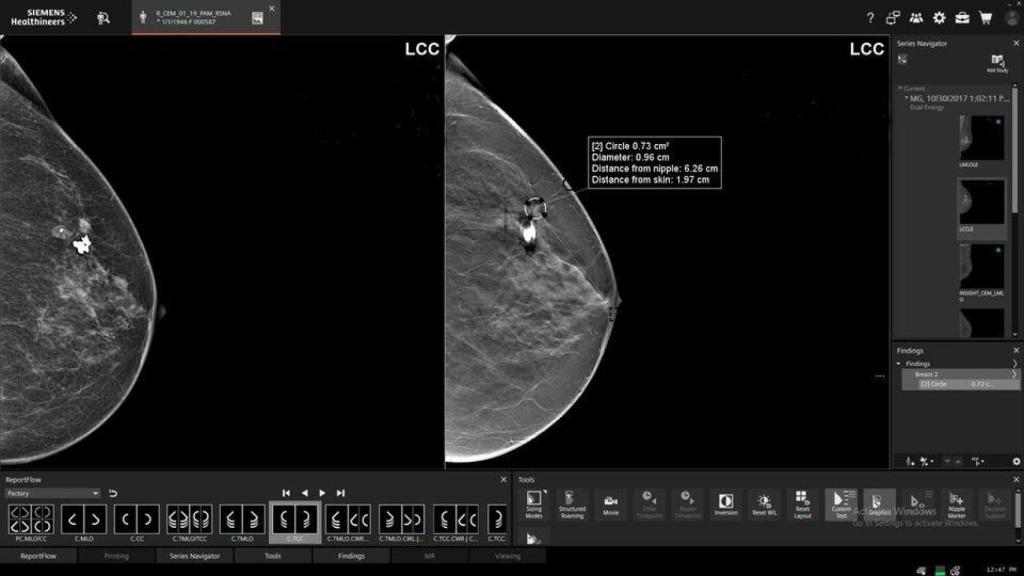

Pruebas de mama en una imagen de archivo.

Pruebas de mama en una imagen de archivo. EP Sevilla